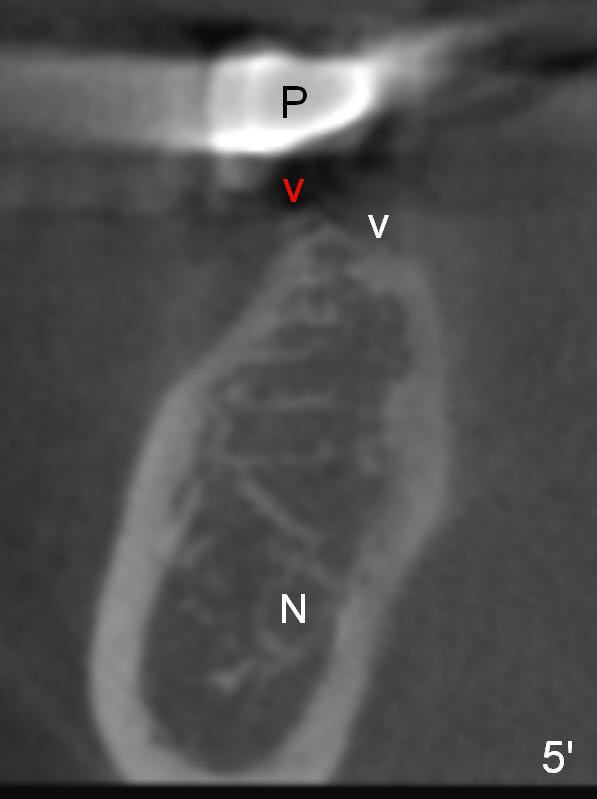

As to #30 osteotomy entry point, it tends to start in the middle of a flat surface (Fig.5' white arrowhead), but it is directly underneath the pontic (P). The trajectory will be not correct. Ideally the entrance point should be at the crest. To avoid slippage, a sharp starter drill will be used. A second advantage is that the osteotomy will be as deep as the previous entry point. There is less likelihood of nerve (N) injury (Fig.5).